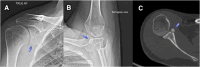

Although the arthroscopic Latarjet procedure has evolved as the most reliable bony sling procedure for shoulder instability with bone loss, the soft cancellous nature of the coracoid makes the FiberTape option for metal-free fixation difficult because of cheese wiring and cutting into the coracoid when the tape is tensioned. Hence, long titanium screws or titanium buttons are used to fix the coracoid in all existing methods for the Latarjet procedure. Rigid and metal-based methods can cause abrasion of the bony moving surfaces coated with cartilage and can cause wear to contact areas, especially when osteolysis occurs during remodeling of the coracoid bone. We describe an absorbable poly lactic acid 3-dimensional printed coracoid protector (which we call the SJ Buckler) to protect the coracoid process resting on its anterior surface and prevent cut through, with laboratory-verified strength to withstand greater than 120 N. This allows us to perform metal-free fixation of the coracoid in the Latarjet procedure, which can be performed arthroscopically or open, where the coracoid tensioning can be done without fear of cut-through. The poly lactic acid material is absorbable and will integrate to bone or disintegrate after the purpose of bony union to glenoid has been achieved.